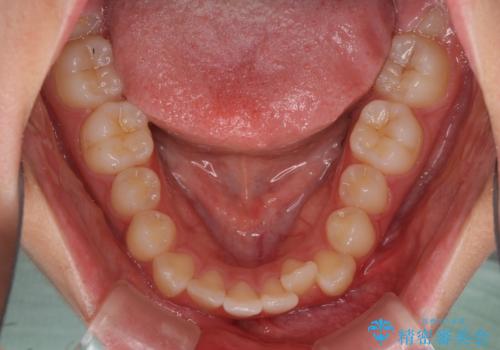

- 口元のデコボコを気にして来院された患者様です。

前歯の捻れにより口元が閉じにくくなっていたため、歯列全体の側方への拡大と、歯と歯の間を少し削ってスペースを獲得することとしました。

ゴムかけをしっかりと行ってもらい、スッキリとした口元に仕上げることができました。